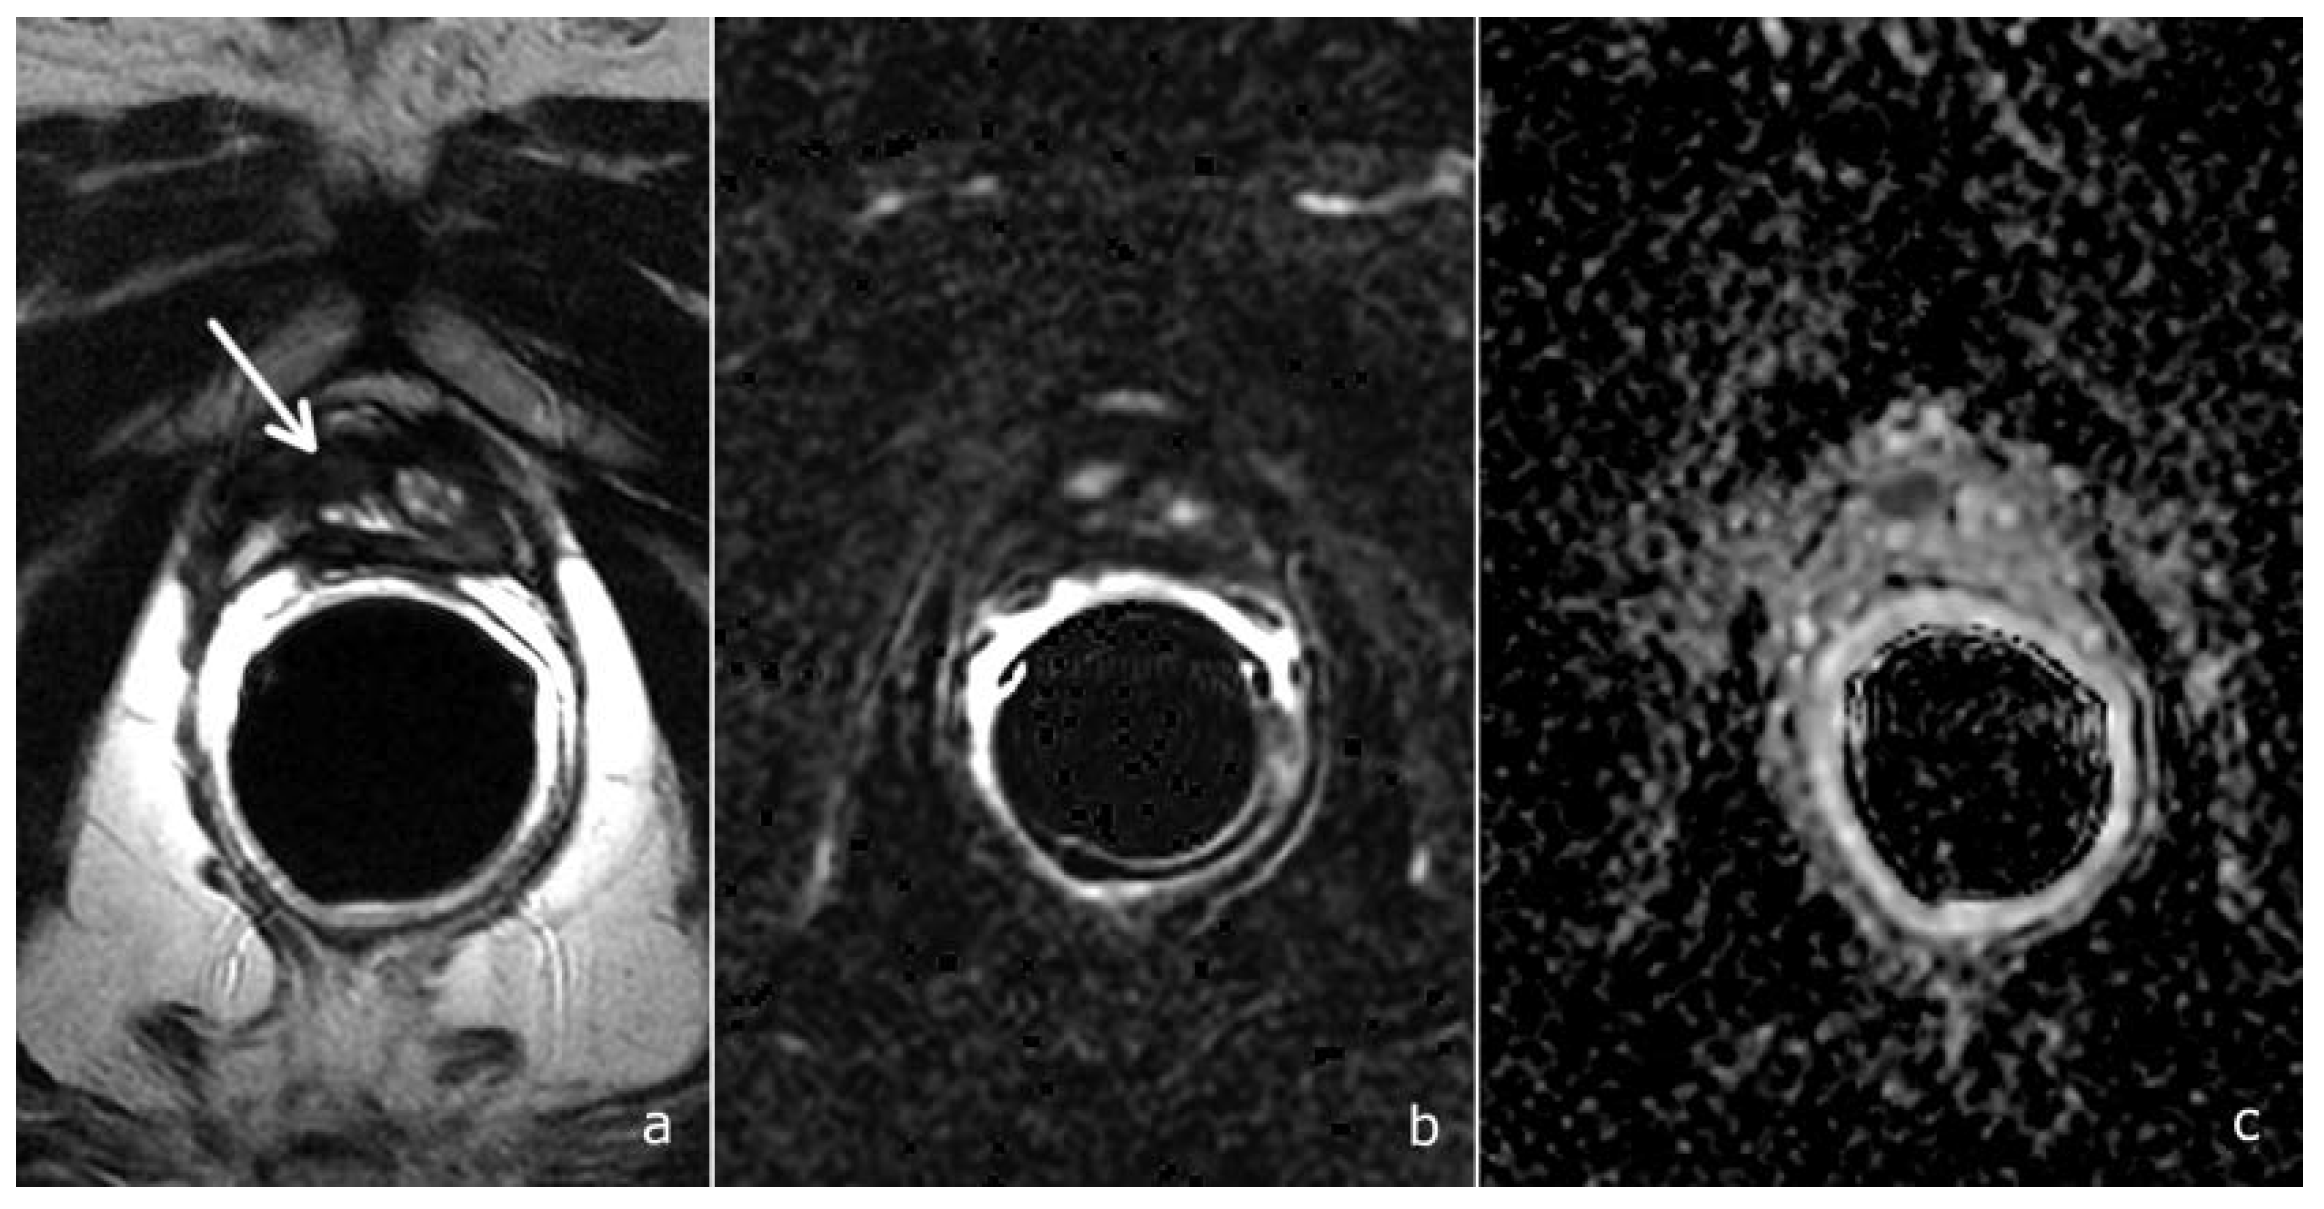

In the setting of suspected local recurrence, the main criticisms of the majority of studies are retrospective analyses, a great variability of the PSA values, a lack of a standard of reference. In most studies, the imaging results were validated using a composite reference standard consisting of heterogeneous parameters (durable PSA control after radiotherapy; concordant findings with other imaging studies; long-term follow-up; consensus achieved by a multidisciplinary board); in others, there was no reference standard, with only the “detection rate” of the imaging test reported [20]. Indeed, histological evidence of suspected local recurrence is not usually required to submit patients to salvage radiotherapy. Also in our study, histological samples were available only for a minority of patients. Nevertheless, we could evaluate the diagnostic accuracy of the PI-RR score: sensitivity and positive predictive value were high (84.6% and 73.0% respectively), while specificity and negative predictive value were low (33.3% and 50%). Overall, the accuracy was 68.4%, slightly inferior to that previously reported [9]. However, the excellent agreement among readers with different levels of experience in mpMRI confirmed the reproducibility of the PI-RR score (Figure 5).

Figure 5.

A PI-RR-score-5 patient, 70 years old, with a PSA value of 0.31 ng/mL. The patient underwent radical prostatectomy for bilateral prostate cancer, Gleason score 4 + 3, with bilateral surgical positive margins at the prostate apex. mpMRI documented a small hypointense tissue in the T2-weighted image, right-sided to the vesico-urethral anastomosis (a-arrow), characterized by intense and early contrast enhancement (b) and restricted diffusion at the ADC map, (c) PI-RR score = 5.